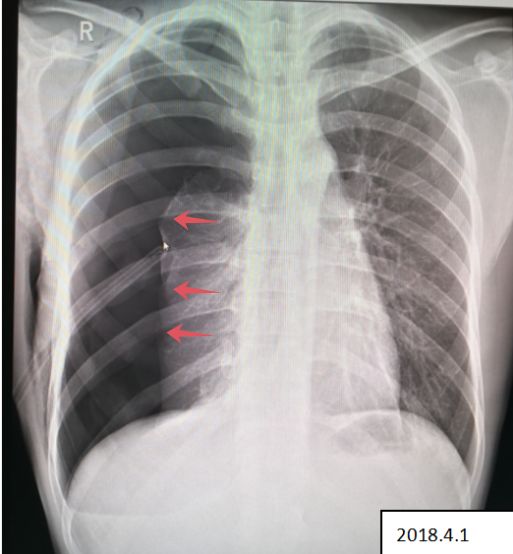

病例6患者的X线胸片

患者右侧肺野内见带状异常透亮无肺纹理区,内侧缘可见发线状被压缩肺组织外缘(红色箭头),被压缩约75%以上,两肺门影不大,肋膈角清晰、锐利,心影形态、大小正常,纵隔稍向左移位。

2018.4.1 患者复查X线图像

患者右肺气胸复查所见:右侧肺野外带(约占肺野4/5)见带状异常透亮无肺纹理区,内侧缘可见发线状被压缩肺组织外缘,被压缩约75%以上,内可见引流管置入影。 右侧胸壁可见气体影。